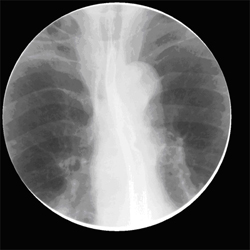

식도암에서 식도조영술 이미지

[식도암에서 식도조영술]

식도조영술은 엑스레이에 비투과성을 가진 물질일 조영제를 입으로 마신 후 조영제가 식도 점막에 묻어 있는 모양을 투시촬영을 통해서 관찰하는 검사법으로 식도점막의 변화를 관찰함으로써 식도암의 모양, 크기, 위치 등을 평가하고 주위 기관과의 관계를 알 수 있습니다.